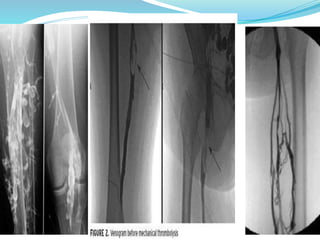

VENOGRAPHY (DIRECT

CONTRAST VENOGRAPHY

 x- ray equivalent of duplex u/s

 most combursome ,invasive imaging technique

 ASCENDING VENOGRAM

1. a vein in dorsum of foot is cannulated

2. tourniquet is applied over malleoli to direct blood

into deep veins

3. non ionic contrast is given

4. gives excellent anatomic information

5. less information when valves have failed

DESCENDING VENOGRAPHY

1. incompetent veins can be shown

2. cannula inserted into femoral vein

3. contrast injected with patient standing

4. contrast is heavier than blood & flows down through

incompetent veins

VARICOGRAM

1 to detect source of recurrent varicose veins

2 contrast is given into one of the varicose veins& followed

to identify source